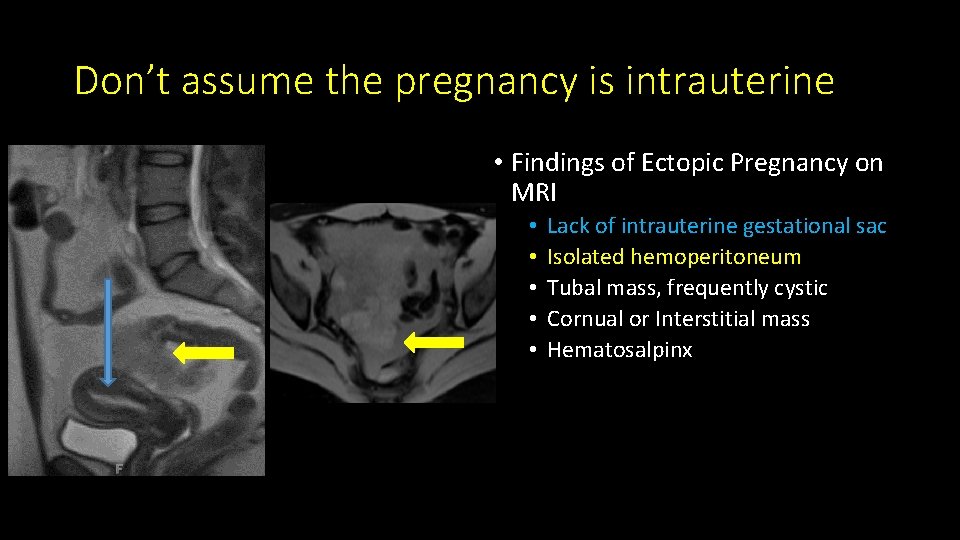

Don’t assume the pregnancy is intrauterine • Findings of Ectopic Pregnancy on MRI • • • Lack of intrauterine gestational sac Isolated hemoperitoneum Tubal mass, frequently cystic Cornual or Interstitial mass Hematosalpinx

Don’t assume the pregnancy is intrauterine • Findings of Ectopic Pregnancy on MRI • • • Lack of intrauterine gestational sac Isolated hemoperitoneum Tubal mass, frequently cystic Cornual or Interstitial mass Hematosalpinx

Don’t assume the pregnancy is intrauterine • Findings of Ectopic Pregnancy on MRI • • • Lack of intrauterine gestational sac Isolated hemoperitoneum Tubal mass, frequently cystic Cornual or Interstitial mass Hematosalpinx

Don’t assume the pregnancy is intrauterine • Findings of Ectopic Pregnancy on MRI • • • Lack of intrauterine gestational sac Isolated hemoperitoneum Tubal mass, frequently cystic Cornual or Interstitial mass Hematosalpinx